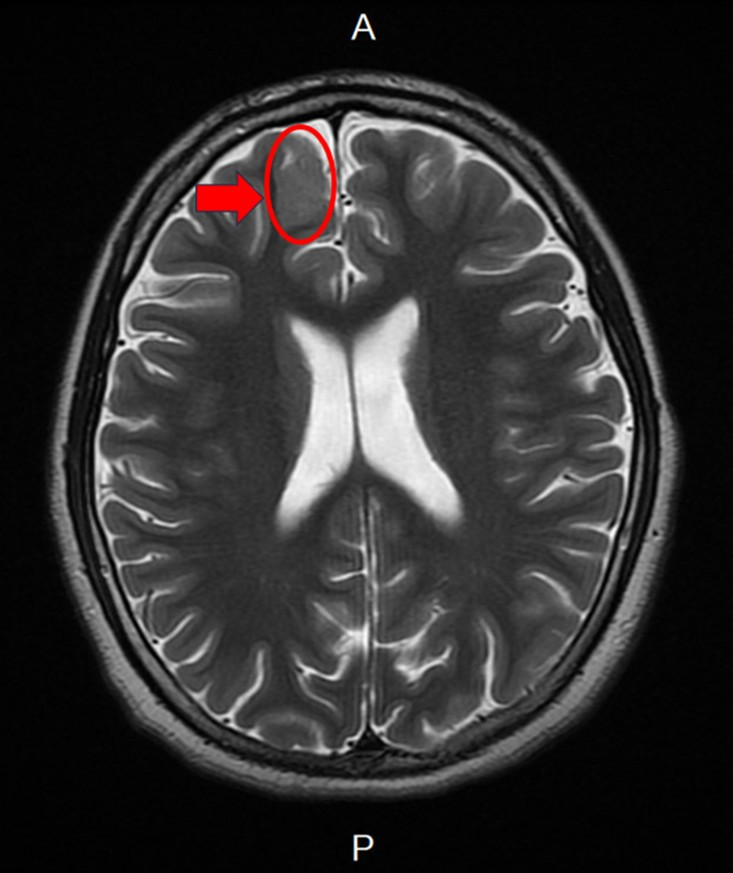

新竹臺大分院小兒部張寶玲醫師評估後發現,男孩腦波檢查出現頻繁右側額葉局部癲癇波,懷疑可能存在腦部病灶。進一步安排腦部磁振造影檢查後,發現右側額葉異常病灶。由於病人屬於頑固性癲癇,在多種抗癲癇藥物治療下仍持續發作,醫療團隊評估後建議接受癲癇手術。

手術過程中透過腦皮質腦波監測,由張寶玲醫師即時判讀並定位癲癇來源,再由神經外科醫師切除病灶。術後病理報告證實為局部腦皮質發育不良(Focal Cortical Dysplasia)。男孩術後恢復良好,未出現併發症,也未再發生意識喪失,癲癇發作次數明顯減少。

張醫師表示,局部腦皮質發育不良屬於腦皮質發展畸形的一種,也是兒童癲癇手術最常見的病理原因。雖然這類病變並非惡性腫瘤,但若引發癲癇,仍需積極評估是否需要外科手術治療。